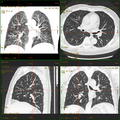

-

Craniale Computertomographie Abgebildet sind Felsenbein und Nasennebenhöhlen. Aufgrund der hohen Auflösung der Aufnahme des verwendeten 64-Zeilen-CTs sind selbst die Gehörknöchelchen erkennbar. -

Koronal reformatierte Darstellung von Abdomen und Becken; gut zu erkennen sind u. a. die Leber und die beiden Nieren. -

Kombination aus multiplanarer Reformatierung und sliding thin slab. Der Bildkursor befindet sich in der Harnblase. Die Originalschichtdicke beträgt 1,25 mm, dargestellt wird in allen Ansichten gemittelt (= average) in 3,7 mm bzw. 3,8 mm Dicke. -

Kombination aus multiplanarer Reformatierung und sliding thin slab. Der Bildkursor befindet sich im rechten Lungenflügel. Die sts-Bildstapel werden in Form von MIP-Darstellungen gezeigt (STS-MIP).[52] Links oben befindet sich eine VR-Darstellung der Lunge; sie zeigt einen Blick auf die koronal an Kursorposition geschnittene Lunge. -